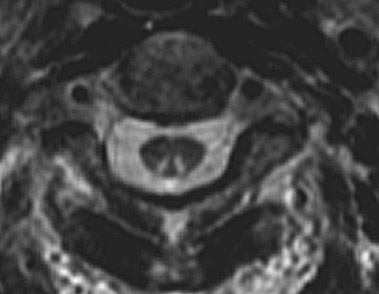

| This axial MRI scan shows changes of subacute combined degeneration of the spinal cord in a patient with pernicious anemia from vitamin B12 deficiency. Note the enhancement of the posterior columns in the region of the cervical cord above and the thoracic cord below. |